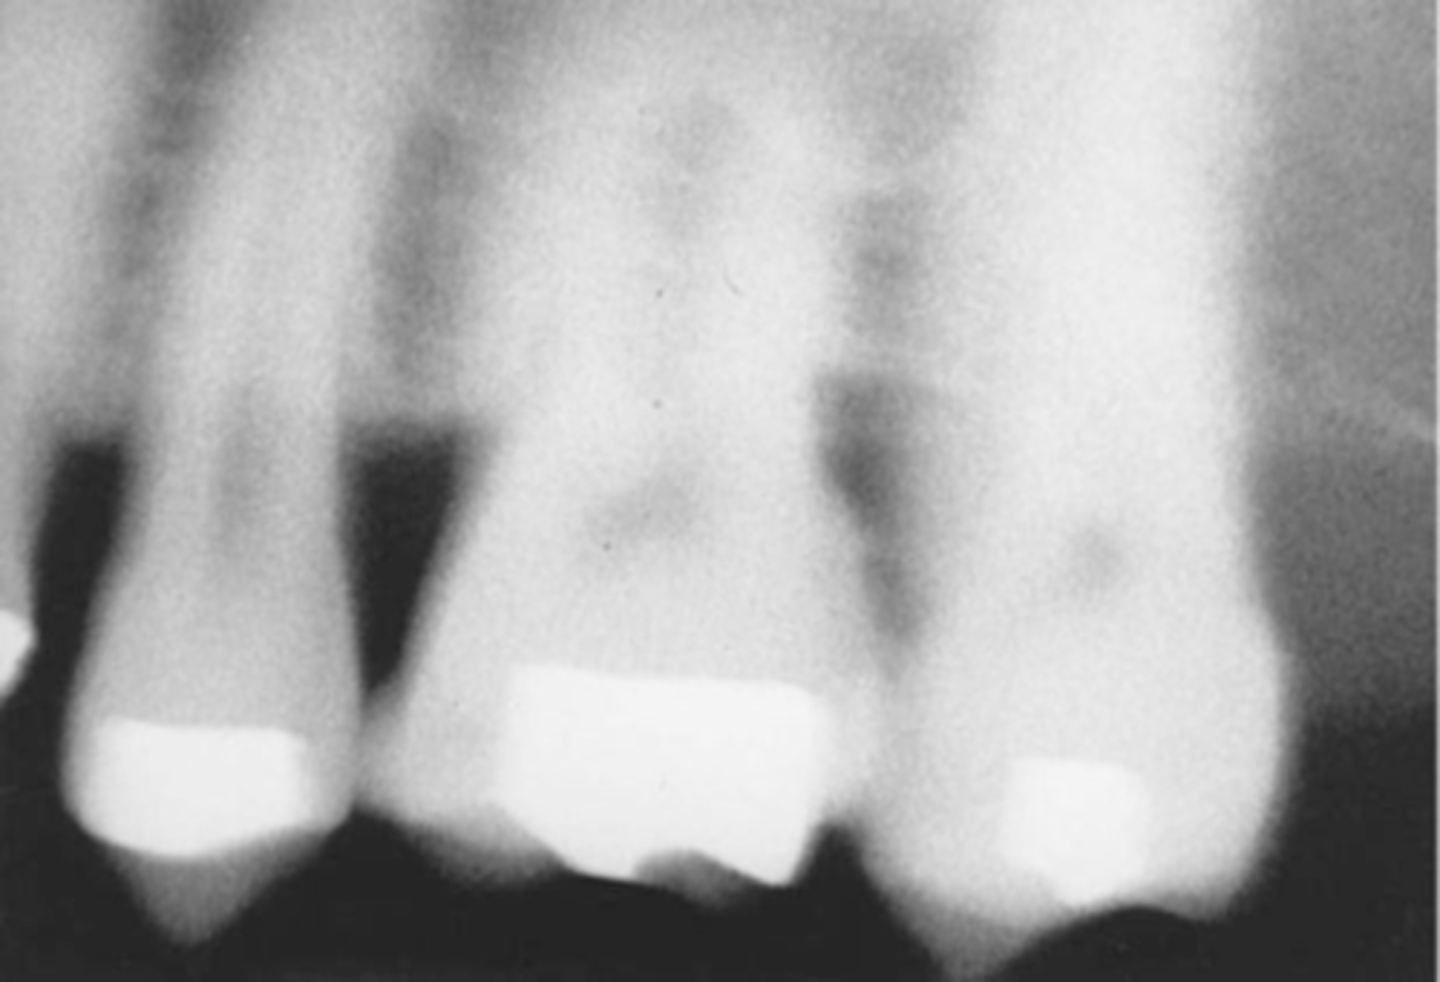

Overexposed Receptor

Results from excessive exposure time, kVp, mA, or a combination of these factors

Time and Exposure Factor Problems-->Overexposed Receptor

-Image appears dark

-Exposed to too much radiation, kVp, mA, or a combination of these

-To prevent check the exposure time, kVp, and mA

Exposure-->Too Dark = Overexposure

-Too high kvp or mA